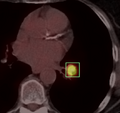

We are developing a Slicer command-line module for PET SUV computation and a wizard interface to a specific workflow for PET SUV computation for longitudinal studies.